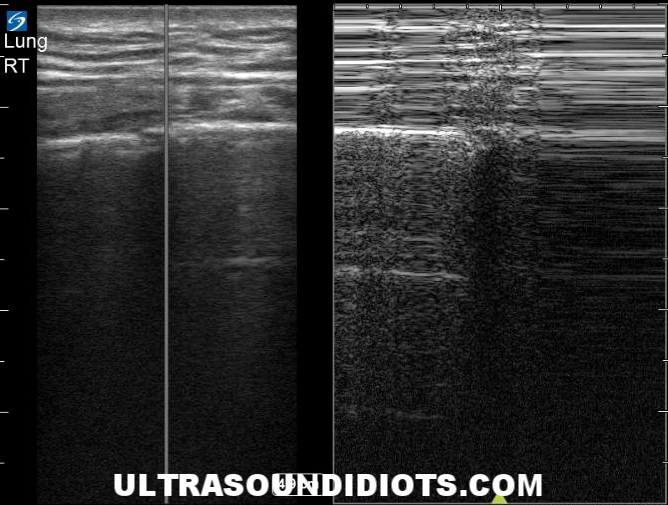

LIMITED CHEST